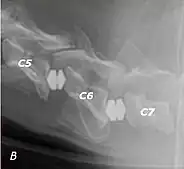

Doberman C6-C7 and C5-C6 traction responsive myelopathy B

T2 weighted MRI in neutral (A) and linear traction (B) of a seven-year-old Doberman with a two-year history of cervical pain treated with NSAIDs and presented acutely tetraplegic: A C6-C7 and C5-C6 traction responsive myelopathy are evident on MRI. The spinal-cord hyperintensity seen at the C5-C6 is suggestive of chronic lesion and most likely responsible for the chronic history of cervical pain, while the C5-C6 lesion was most likely responsible for the acute tetraplegia.